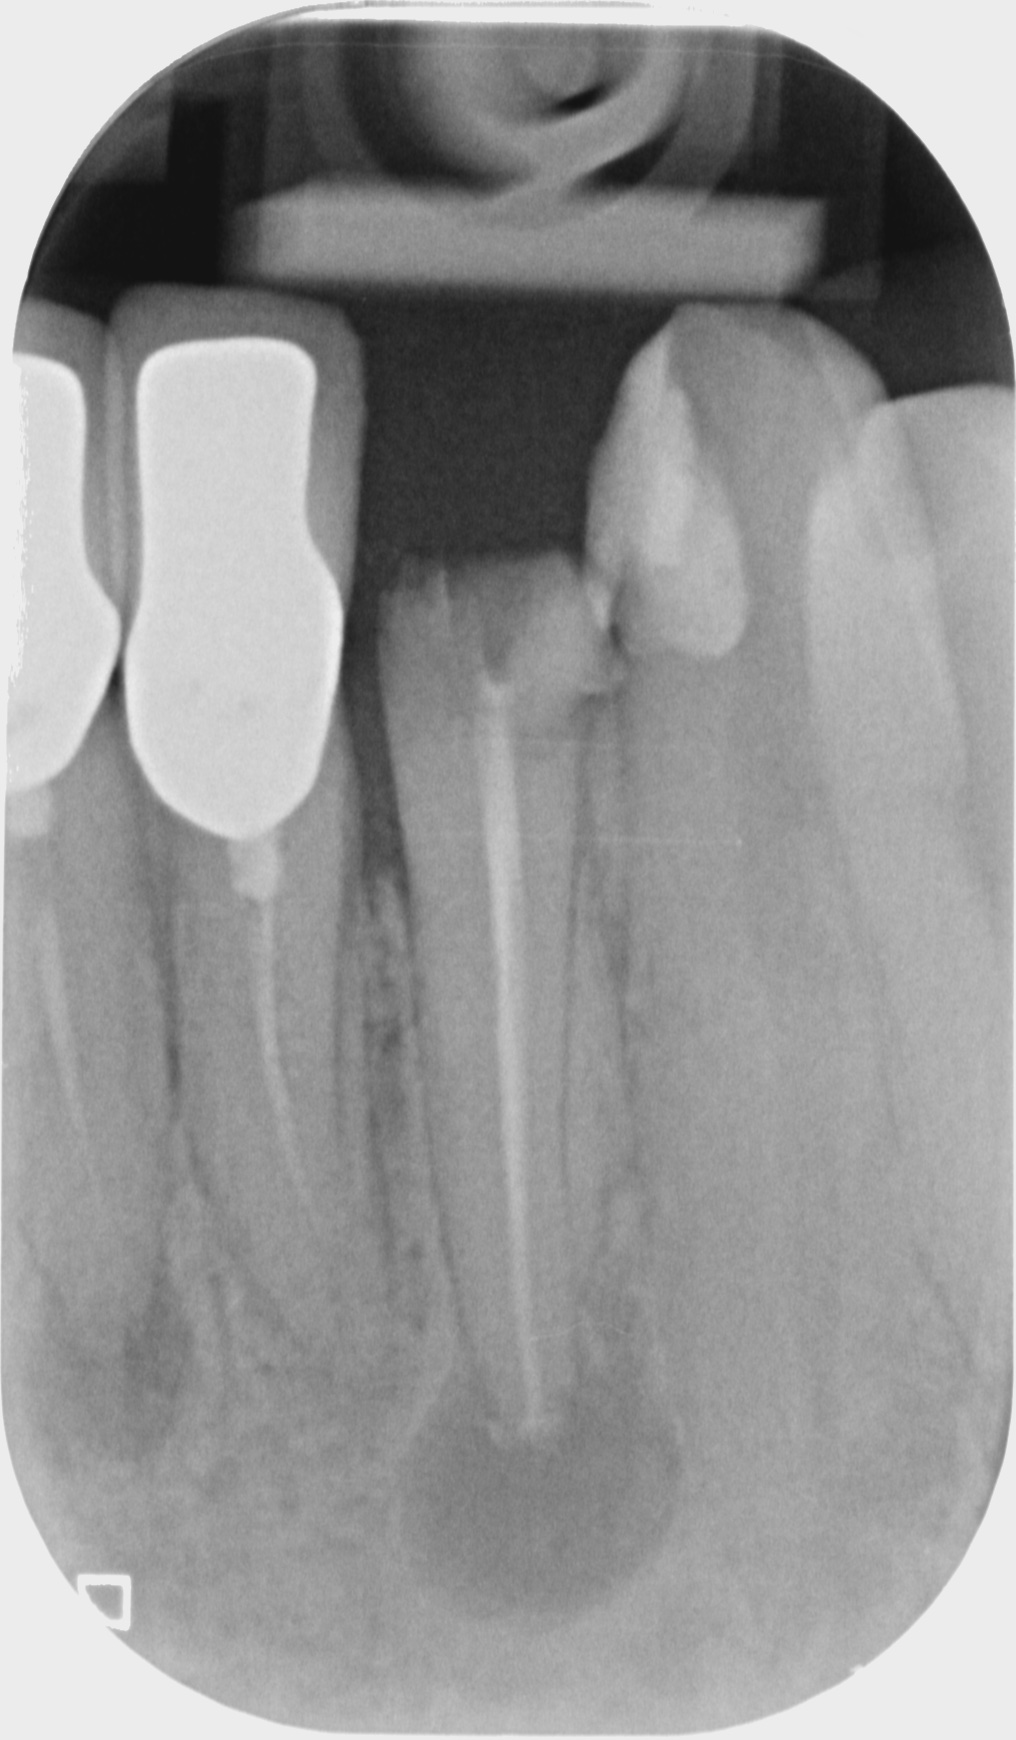

Fallbeispiele

Zum Vergrössern klicken